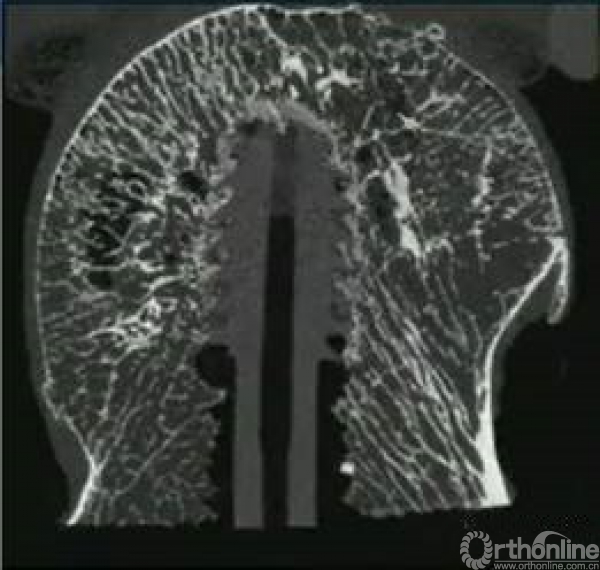

骨质疏松也会影响内固定在股骨头内的稳定性。

疏松的骨质不适合使用螺钉稳定,而更适合螺旋刀片打压。

同时,双钉可以更好的预防头钉切出。